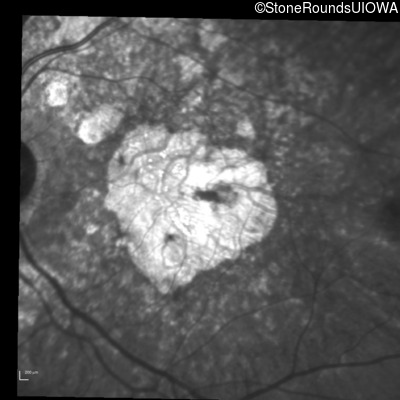

Age at visit: 62 years

This 62 year old man first noted mild distortion in his vision in his 30's, but has always been correctable to 20/20. One year ago an optometrist told him there were pigment abnormalities in his macula.

Diagnosis & molecular findings

Disease Gene Allele 1 variant(s) Allele 2 variant(s) Inheritance mode

Pattern Dystrophy PRPH2 Lys153Glu AAG>GAG   AD